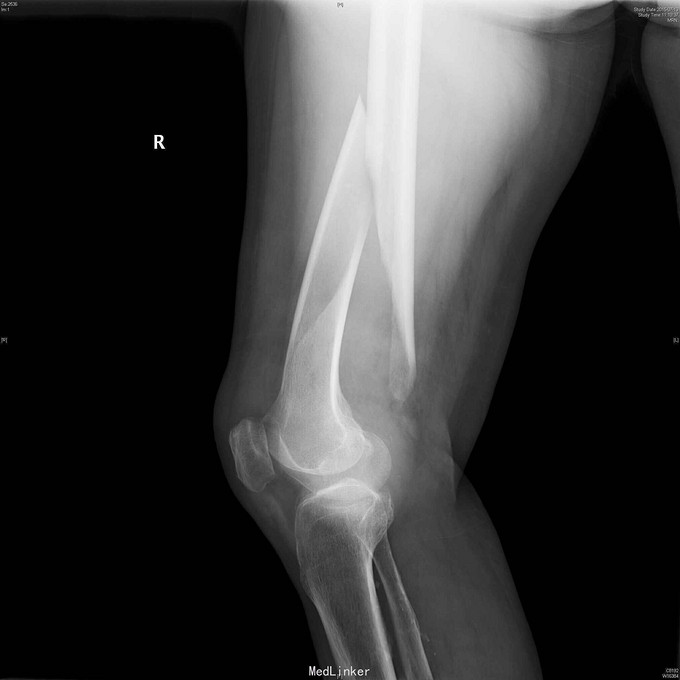

83岁女性,摔倒跪地致右大腿肿胀,疼痛,短缩内翻畸形一天。

查体:右大腿中下段肿胀明显,淤血,压痛,短缩畸形。小腿感觉正常,足背动脉搏动好。 右股骨正侧位片:右股骨中下段长螺旋形骨折,移位短缩明显。